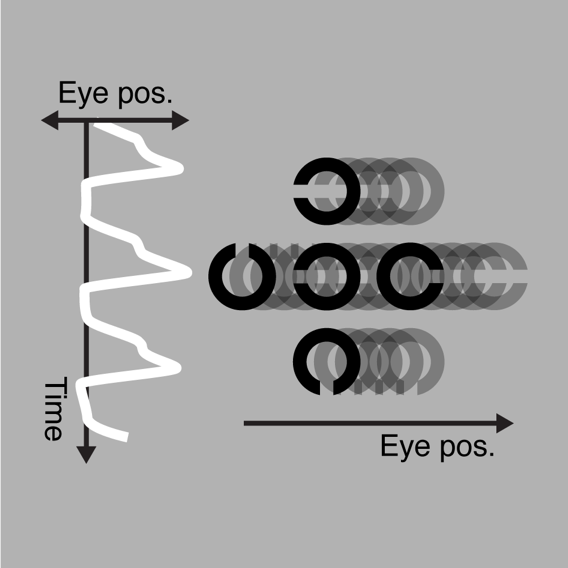

infantile nystagmus

Infantile nystagmus (sometimes referred to as congenital nystagmus) is a visual disorder characterised by involuntary eye movements, with associated deficits in visual acuity. Given reports that elevations in crowding may also arise in these instances, we have been examining the properties of crowding in congenital nystagmus in order to test whether the origin of these effects lies in the same mechanism as crowding in amblyopia and the typical visual periphery (as above).

- Tailor, VK, Theodorou, M, Dahlmann-Noor, AH, Dekker, TM, & Greenwood, JA (2021). Eye movements elevate crowding in idiopathic infantile nystagmus syndrome. Journal of Vision, 21(13):9, 1-23. [Download]